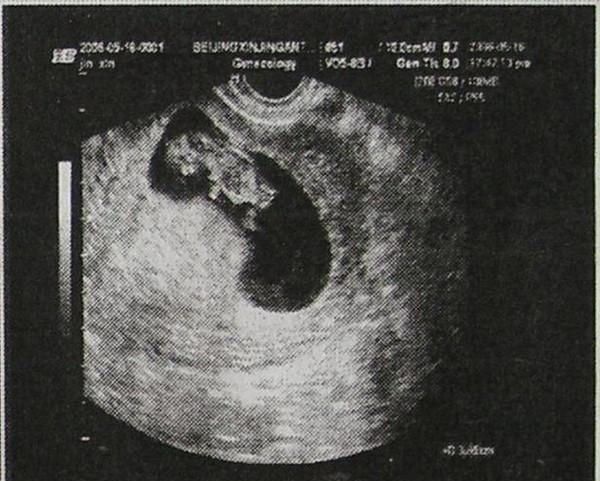

60天女孩胎囊图片,男宝b超图9周

我60天的时候做彩超医生告诉我是双胎有两个孕囊有明显的胎心搏动.

怀孕60天查的.

孕囊图片60天

怀孕60天男孩孕囊图